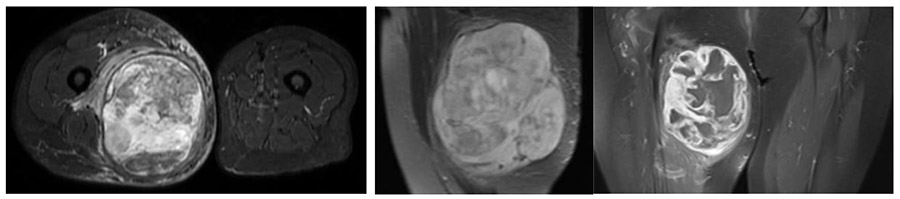

Ameliyat Öncesi: MR’da uyluk iç kısımda damar sinir paketini ittiren, düzensiz sınırlı heterojen, periferik ödemin eşlik ettiği yumuşak doku kitlesi görülmekte